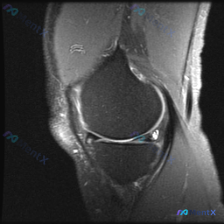

单一切面膝关节MRI,这个半月板信号异常大家怎么看?

刚看到一份膝关节MRI单矢状位切面的读片需求,核心问题是观察半月板异常,我整理了完整的分析思路分享给大家。

这是一张膝关节矢状位MRI影像,根据信号特征判断:不符合典型T1加权像(骨髓信号偏低,关节软骨、积液呈高信号),更符合质子密度加权像(PDWI)或T2加权像,这类序列对半月板、软骨损伤评估更敏感。

骨髓信号未见明显局灶异常,无明显骨水肿;股骨髁和胫骨平台关节软骨信号尚可,无明显剥脱或严重软骨缺失;前交叉韧带走行连续,信号正常;髌韧带形态信号无异常;关节腔内无明显大量积液。

核心异常:半月板体部可见明显线状/楔形高信号,且高信号贯穿半月板上下关节面,病灶也可能位于后角附近区域。

看到贯穿半月板关节面的高信号,第一反应就是半月板撕裂,这是典型的Ⅲ级半月板信号改变。但我们还是要走一遍鉴别流程,避免踩坑。

结合现有单一切面影像信息,最符合的诊断是半月板Ⅲ级撕裂,创伤性撕裂可能性最高,退变性撕裂次之,其他病因可能性极低。

不过需要明确的是:本病例仅提供了单一矢状位切面,要确定撕裂的具体分型(纵裂、横裂、桶柄状撕裂等)、范围,以及排除伴随损伤(韧带损伤、骨挫伤等),必须结合冠状位、轴位和其他序列的影像综合评估。临床也需要结合患者病史、体格检查(麦氏征等)进一步确认,再决定后续治疗方案。